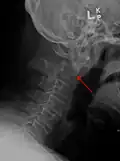

Fractures

Repair of a dens fracture

A fracture of both pedicles of the axis is termed a Hangman's fracture.

Fractures of the dens are classified into three categories according to the Anderson Alonso system:

• Type I fracture - Extends through the tip of the dens. This type is usually stable.

• Type II fracture - Extends through the base of the dens. It is the most commonly encountered fracture for this region of the axis. This type is unstable and has a high rate of non-union.

• Type III fracture - Extends through the vertebral body of the axis. This type can be stable or unstable and may require surgery.[1]